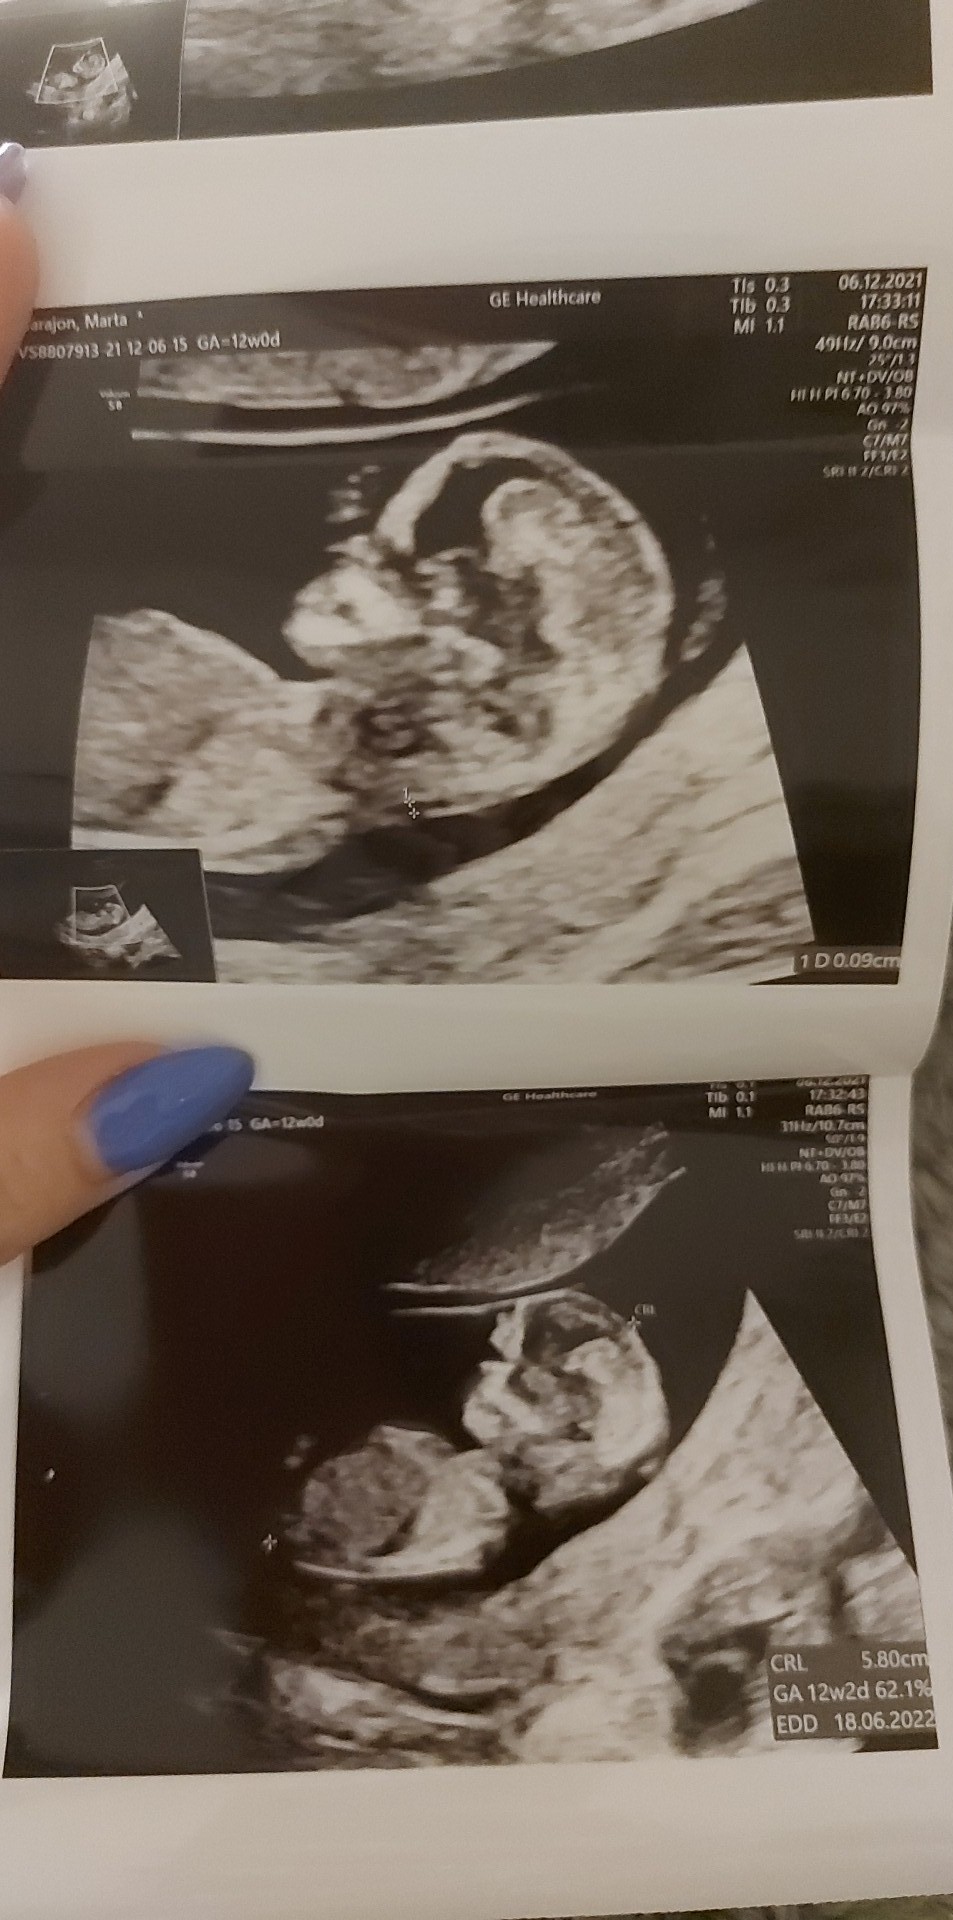

A teraz poszłam na prenatalne i lekarz był mało wylewny. Nie wiem nic. Płci jeszcze nie widać ogólnie powiwdzial że wygląda to dobrze ale mam brać acard bo przepływ krwi jest taki sobie. I nawet nie wiem jak dostanę wyniki i w ogóle. Krew na pappa pobrana. 9 idę do swojego gina i się dowiem co i jak bo serio nie wiem co mam myśleć.